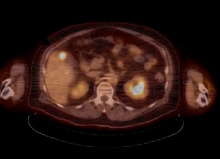

Piramal Imaging SA, a division of Piramal Enterprises, announced that the U.S. Food and Drug Administration (FDA) and the European Medicines Agency (EMA) have accepted its applications for review of the investigational positron emission tomography (PET) amyloid imaging agent [18F] florbetaben. A New Drug Application (NDA) was submitted to the FDA and a Marketing Authorization Application to the EMA for [18F] florbetaben use in the visual detection of beta-amyloid in the brains of adults with cognitive impairment who are being evaluated for Alzheimer's disease and other causes of cognitive decline. [18F] florbetaben binds to beta-amyloid plaques in the human brain, a hallmark characteristic in Alzheimer's disease.